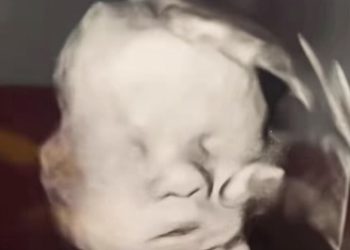

Read moreDetailsFotografija ultrazvuka koja se nedavno proširila društvenim mrežama izazvala je oduševljenje i suze u očima mnogih vjernika diljem svijeta. Na...